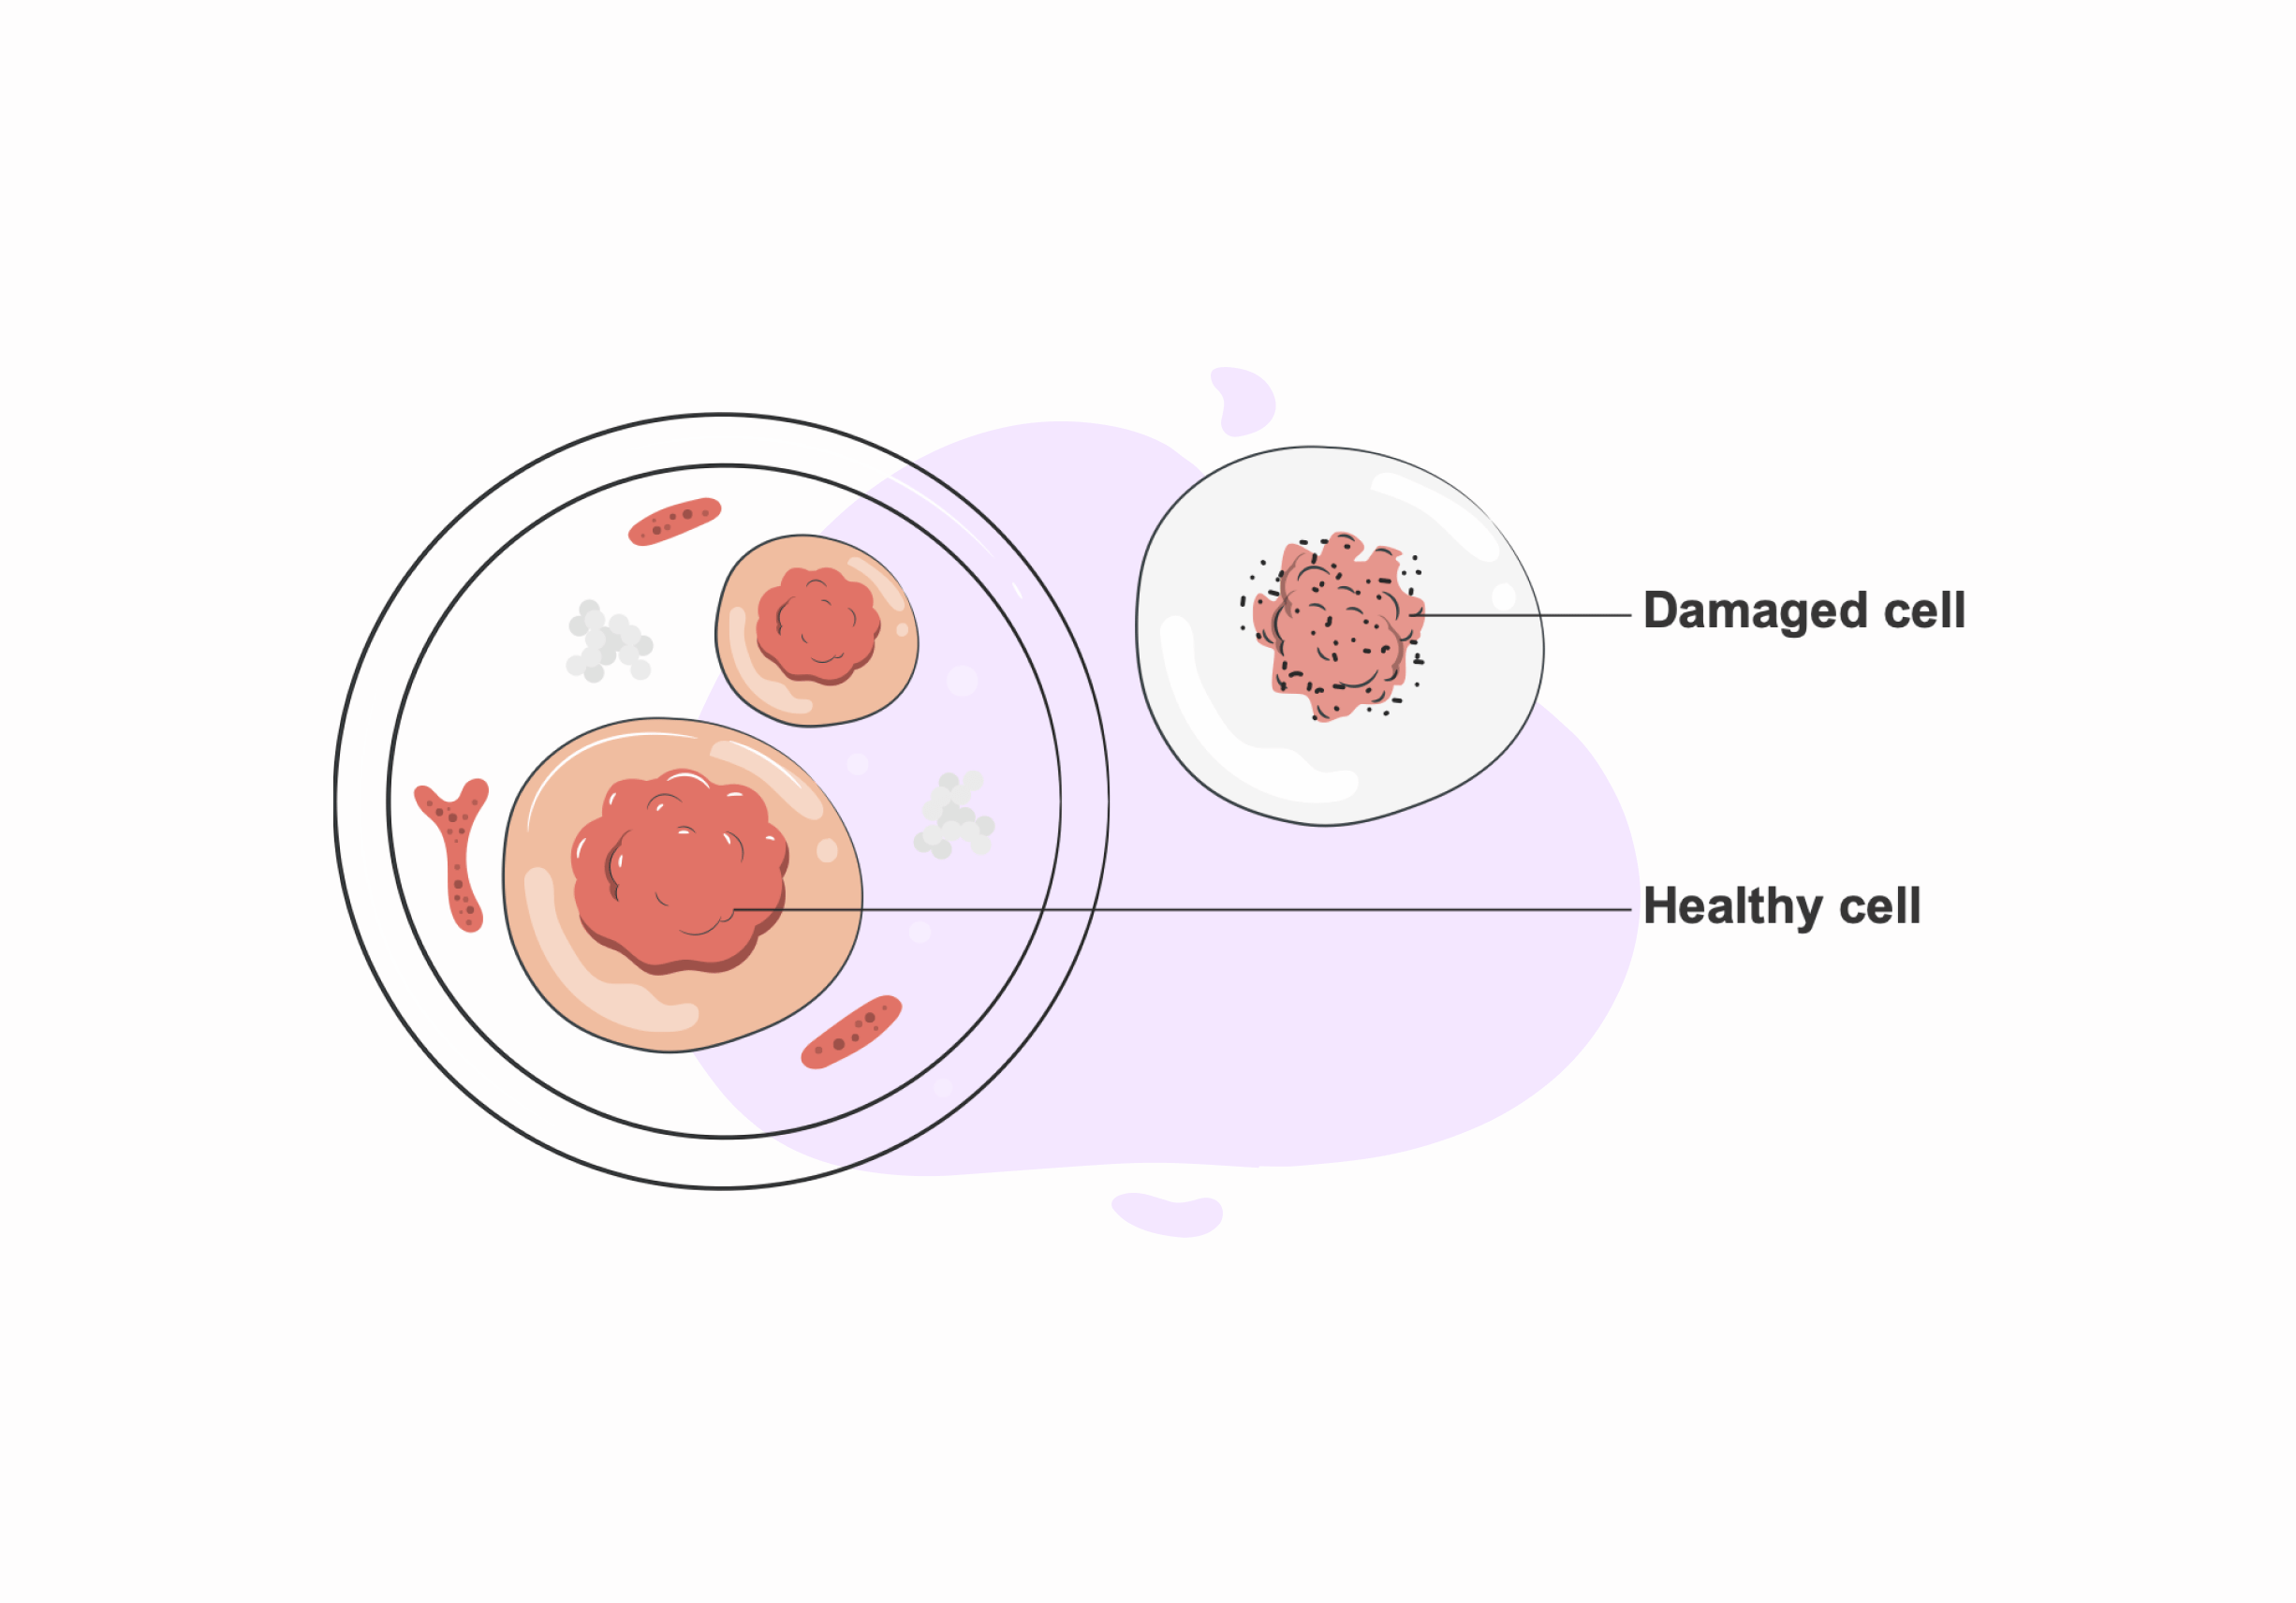

6. Cellular Damages

Excess ozone exposure for a longer duration may trigger cell damage and dysfunction. Thus, it is leading to metabolic alterations.